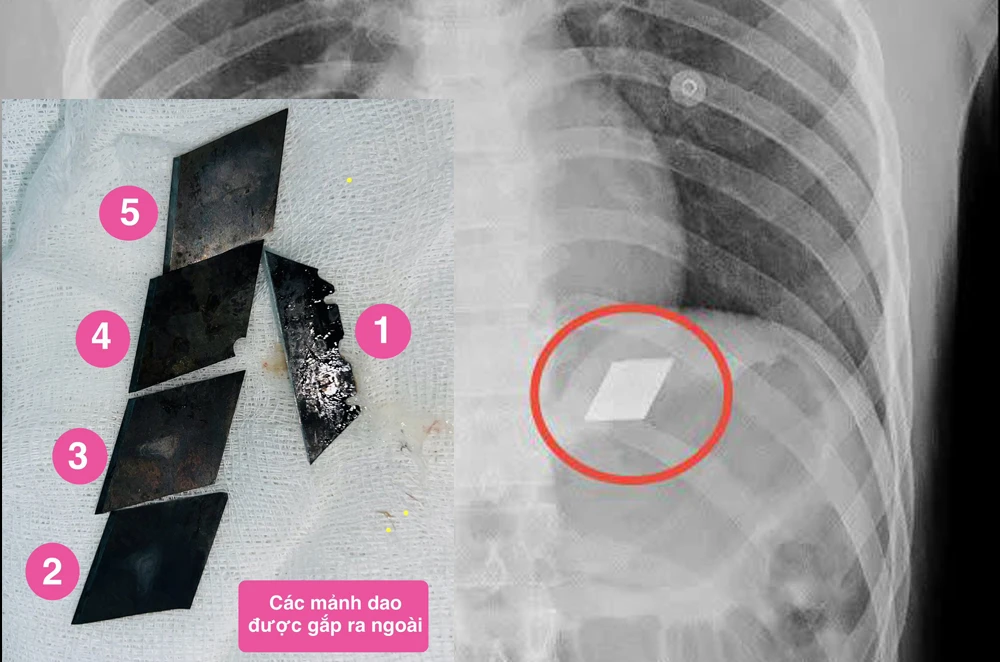

Lưỡi dao rọc giấy và dao lam nằm trong bụng nam bệnh nhân được các bác sĩ gắp thành công ra ngoài. Ảnh: BV

Đại diện Bệnh viện Đa khoa tỉnh Bình Dương cho biết bệnh nhân L (26 tuổi), nhập viện trong tình trạng đau bụng dữ dội và khó thở. Sau khi siêu âm, các bác sĩ phát hiện phát hiện có dị vật sắc nhọn nằm trong thực quản và dạ dày của bệnh nhân.

Ngay lập tức, các y bác sĩ đã họp để chẩn đoán và đưa ra phương án can thiệp khẩn cấp. Sau đó, các bác sĩ đã tiến hành nội soi dạ dày. Tiếp đến, các bác sĩ đã dùng phương pháp nội soi để gắp một nửa dao lam đang bị kẹt ở miệng thực quản. Đồng thời, gắp 4 mảnh lưỡi dao rọc giấy ra khỏi dạ dày của bệnh nhân.

Toàn bộ quá trình diễn ra suôn sẻ, tránh được những tổn thương nghiêm trọng cho đường tiêu hóa. Sau can thiệp nội soi, bệnh nhân được theo dõi sát sao. Hiện tại, sức khỏe của nam bệnh nhân nuốt dao lam, dao rọc giấy này đã ổn định.

Theo các bác sĩ, đây là một ca nội soi hi hữu, phức tạp và nguy hiểm, đòi hỏi kỹ thuật cao và sự khéo léo của đội ngũ y bác sĩ. Việc gắp các lưỡi dao sắc nhọn ra ngoài mà không gây tổn thương thêm cho thực quản và dạ dày đòi hỏi kỹ năng chuyên môn rất cao và sự cẩn trọng tuyệt đối.